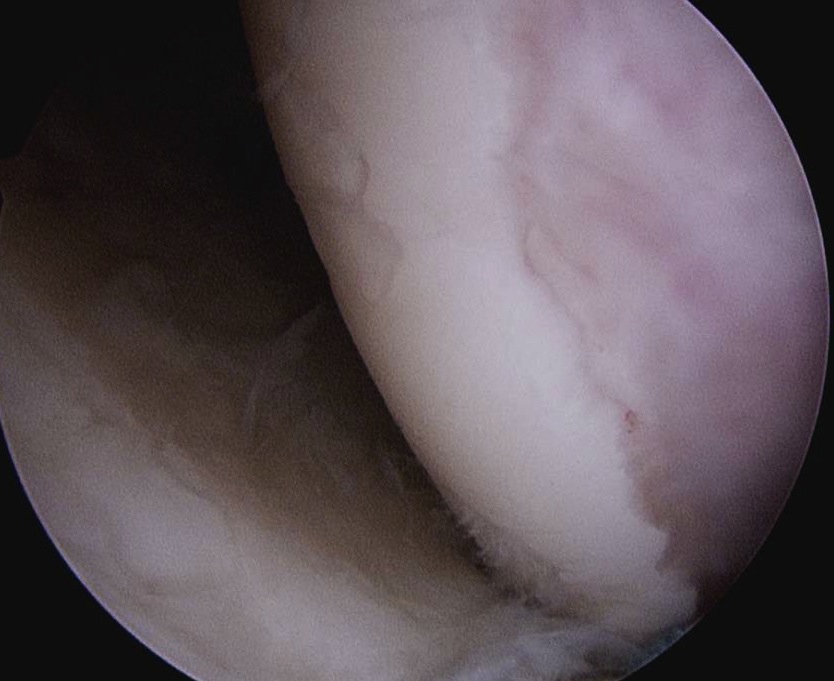

- view from anterior portal

- posterior cannula over Hill Sachs lesion

- debride base of Hill Sachs to bleeding bone

End result